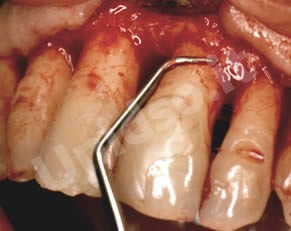

L’ Unità Operativa di Parodontologia e Igiene Orale si compone di 5 sezioni. L’attività’ clinico-assistenziale è svolta da diversi odontoiatri, supportata da igienisti dentali e assistenti alla poltrona, ed è articolata sulla base di appuntamenti programmati. Nell’Unità Operativa di Paradontologia e Igiene Orale del DSMOB si eseguono le seguenti prestazioni odontoiatriche: istruzioni d’igiene orale, ablazione tartaro, full radiografico, terapia dell’alitosi, levigatura radicolare, chirurgia parodontale riparativa, resettiva e rigenerativa e chirurgia plastica dei tessuti molli parodontali.